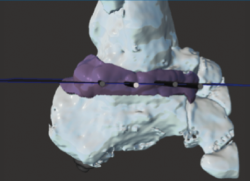

Figura 12. Guía 3D para la resección de la pseudoartrosis.

Utilidad de la impresión 3D: se decidió imprimir una guía 3D de corte como ayuda intraoperatoria. La guía permite la resección de la coalición de manera completa y reducir la necesidad de guía con fluoroscopia.

- Identificación del plano de pseudoartrosis (Figura 11).

- Diseño de la guía de corte guiada por aguja de Kirschner (Figura 12).